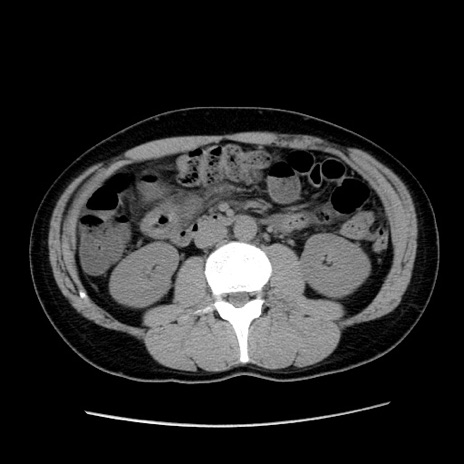

症例36(横断像)

【症例】20歳代 男性

【主訴】心窩部痛

【現病歴】今朝より上腹部痛あり。一旦軽快していたが再度出現したため救急要請。昨日夕に白身の魚を含む刺身を食べた。

【身体所見】BP 136/89mmHg、HR 74/min、BT 37.0℃、腹部:膨満、軟、心窩部に圧痛あり。反跳痛なし、筋性防御なし、腸雑音やや亢進あり。

【データ】WBC 17700、CRP 0.48